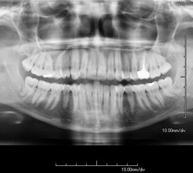

Técnica mediante la cual, utilizando rayos X, se obtienen imágenes de los senos paranasales para su estudio. Indicaciones: dificultad respiratoria nasal, tos crónica, cefalea, mucosidad. - RX ATM (Articulación Temporo-Mandibular)

Técnica mediante la cual, utilizando rayos X, se obtienen imágenes de la articulación temporo-mandibular para su estudio. Indicaciones: traumatismo, dolor al masticar, ruido al masticar, limitación en la apertura bucal. - RX Cavum